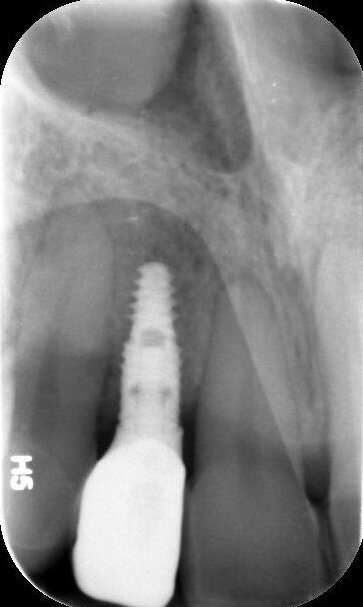

Door de regulatie van de cuspidaten naar distaal is botappositie opgetreden, waardoor bij het plaatsen van de twee implantaten een minimale botopbouw volgens een GBR-techniek noodzakelijk was (afbeelding 7-9). Via digital smile design werd de uiteindelijke vorm gesimuleerd (afbeelding 10 en 11). Er werden twee verschroefde zirkonium kronen met opgebakken porselein vervaardigd voor de implantaten en er werden facings van lithiumdisilicaat gemaakt bij de centrale incisieven en cuspidaten (afbeelding 12-17).